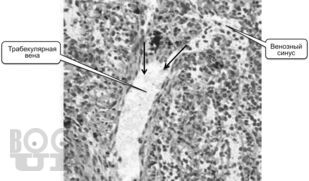

Учебное пособие к практическим занятиям по частной гистологии. Органы кроветворения и иммунной защиты, эндокринная система

Пособие предназначено для самостоятельной работы студентов медицинских вузов на практических занятиях по частной гистологии.